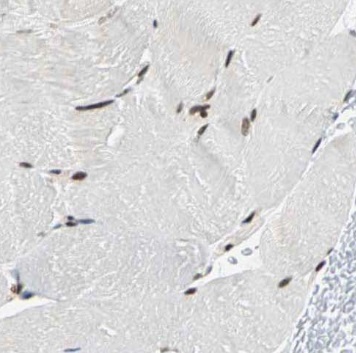

| 验证图片 | Immunohistochemistry of paraffin-embedded human skeletal muscle using FNab05888(NUBP2 antibody) at dilution of 1:50 L02 cells were subjected to SDS PAGE followed by western blot with FNab05888(NUBP2 antibody) at dilution of 1:500 |